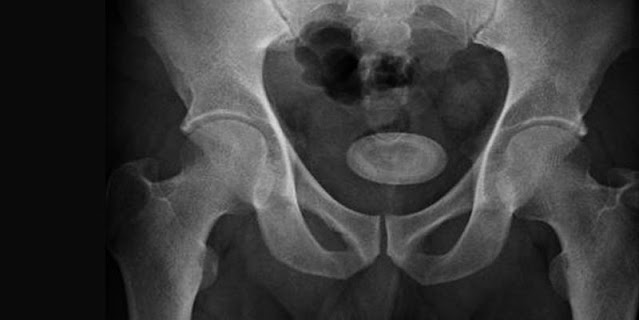

Hard masses of minerals that are present in the bladder are known as bladder stones. They occur when the urine in the bladder becomes concentrated, causing the minerals in the urine to crystalize. Concentrated urine that lies in the bladder for longer periods is often the result of not completely emptying the bladder.

When it comes to treating bladder stones, which are solid mineral deposits that develop inside the bladder, a cystolitholapaxy is the most efficient surgical procedure. A cystoscope is introduced inside the bladder during a cystolitholapaxy procedure to locate bladder stones. It is like a tiny telescope. With the help of a laser, the stones are fragmented into small particles, which are then removed from the body.